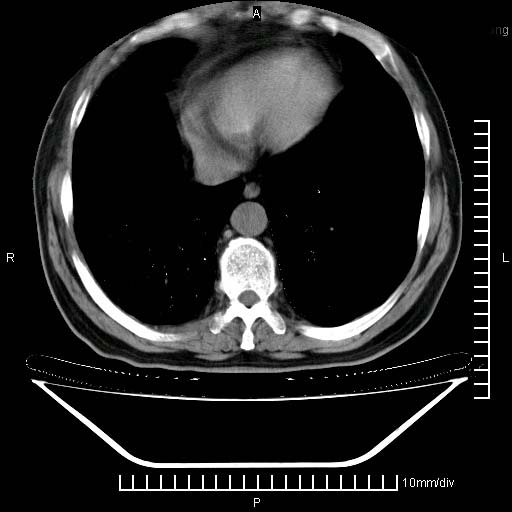

标题: CT24043:胸部增强:男性,60岁

既往肺结核,近10几天,咳嗽,咳痰,右侧胸痛,疼痛较明显,右上肺斑块考虑结核灶胸膜粘连,增强,可惜动脉期没有定好,未见强化,可延迟4分后又见较明显强化,中心见低密度影,如果说结核是边缘强化,可这个灶强化的面积挺大的,让人很挠头。

1)两肺继发性肺结核。2)右侧胸膜增厚+少量胸腔积液。